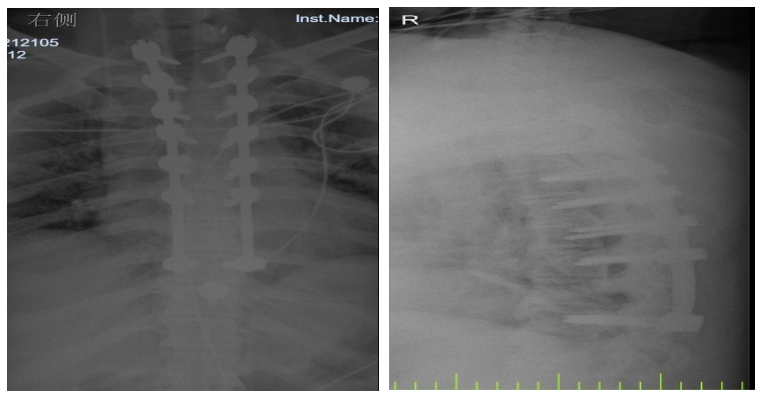

入院后,國(guó)文醫(yī)院骨科迅速組織多名專家會(huì)診,并為吳先生完善了頸椎及胸椎的 MRI 檢查。結(jié)果顯示,吳先生的頸椎及胸椎多階段嚴(yán)重椎管狹窄,脊髓壓迫超過 50%,情況十分危急。經(jīng)過骨科專家團(tuán)隊(duì)的綜合會(huì)診及評(píng)估,最終為他制定了一套個(gè)性化的治療方案,包括頸椎后路單開門椎管減壓頸椎融合內(nèi)固定術(shù),以及胸椎間盤切除伴椎管減壓胸椎植骨融合內(nèi)固定術(shù)。在完善術(shù)前檢查、確認(rèn)無手術(shù)禁忌后,骨科主任呂國(guó)福如期為吳先生實(shí)施了手術(shù)。

手術(shù)涉及頸椎及胸椎多個(gè)階段,操作難度極大。專家團(tuán)隊(duì)采用 “蠶食法” 減壓,分塊去除增生韌帶,最大程度減少對(duì)脊髓的損傷;同時(shí)運(yùn)用椎弓根螺釘固定技術(shù),確保手術(shù)部位的穩(wěn)定性。

術(shù)后 3 天,吳先生的下肢肌力就從 3 級(jí)恢復(fù)到了 4 級(jí);術(shù)后 1 個(gè)月,胸部束縛感明顯緩解;術(shù)后 3 個(gè)月,他已經(jīng)能夠重返工作崗位,生活基本恢復(fù)正常。